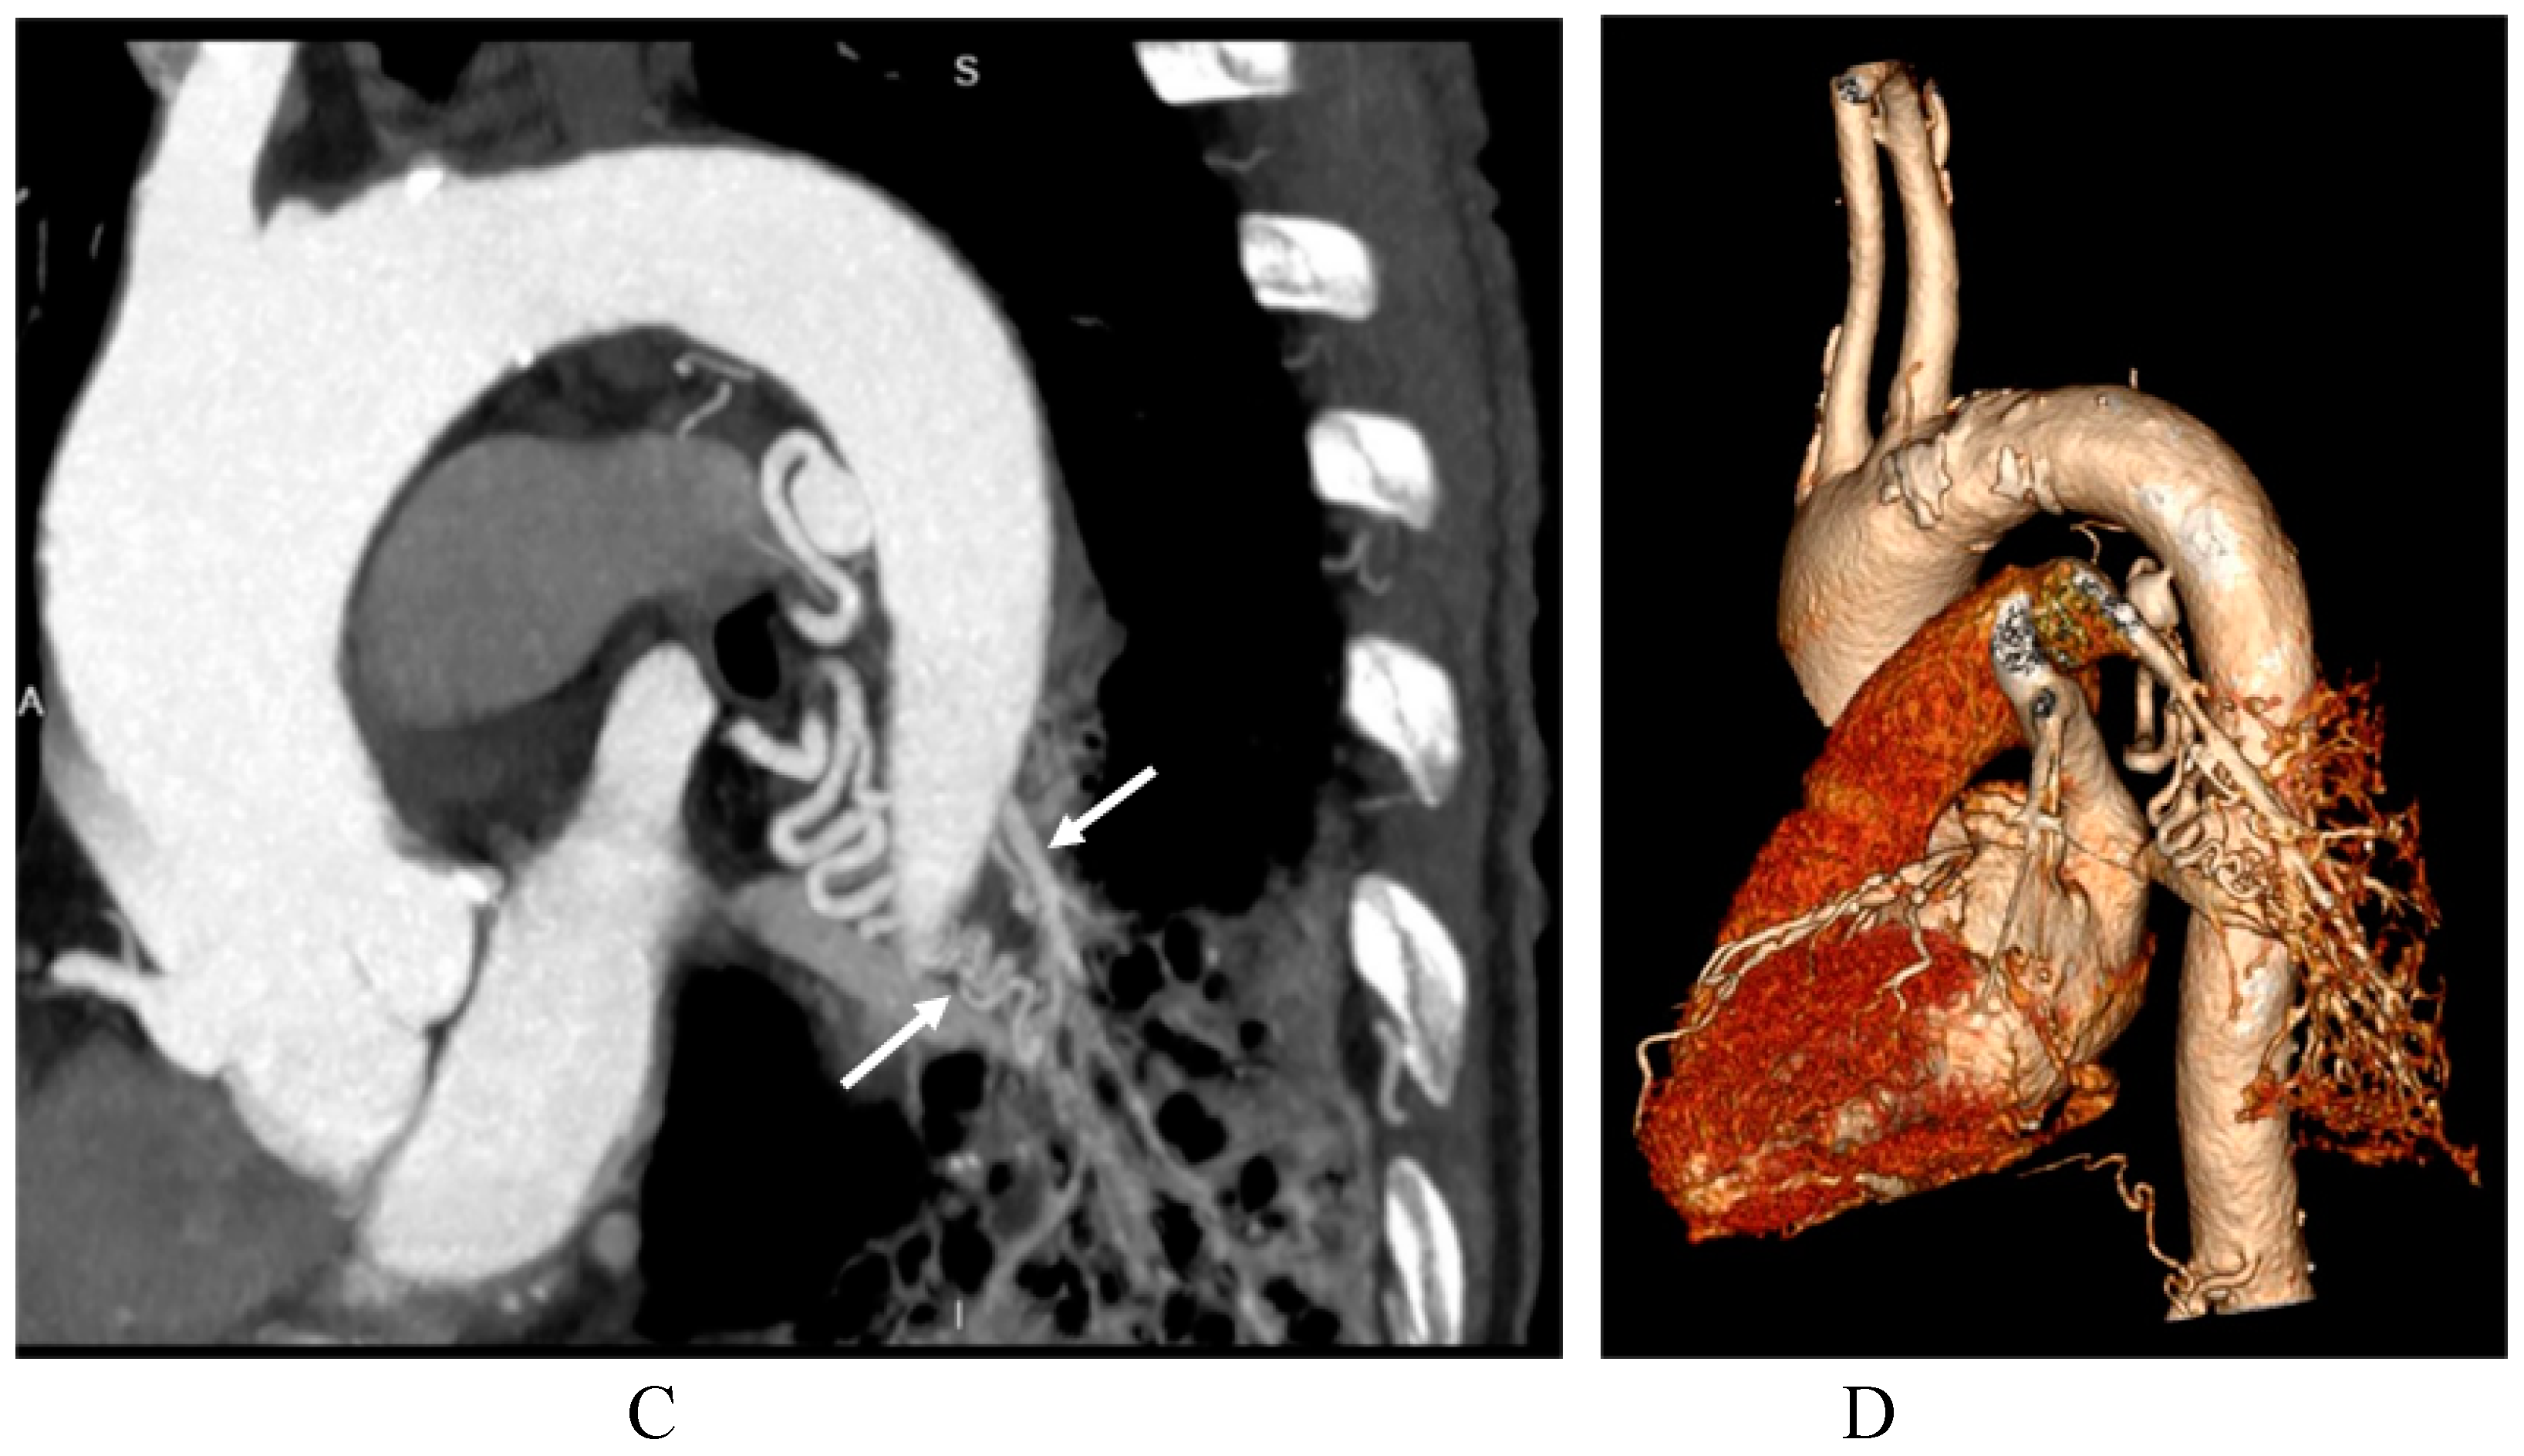

3.2. Imaging appearances of CTPA

- Long, Q.; Zha, Y.; Yang, Z. Evaluation of pulmonary sequestration with multidetector computed tomography angiography in a select cohort of patients: A retrospective study. Clinics. 2016, 71, 392–398. [Google Scholar] [CrossRef]

- Yue, S.W.; Guo, H.; Zhang, Y.G.; Gao, J.B.; Ma, X.X.; Ding, P.X. The clinical value of computer tomographic angiography for the diagnosis and therapeutic planning of patients with pulmonary sequestration. Eur. J. Cardiothorac. Surg. 2013, 43, 946–951. [Google Scholar] [CrossRef] [PubMed]